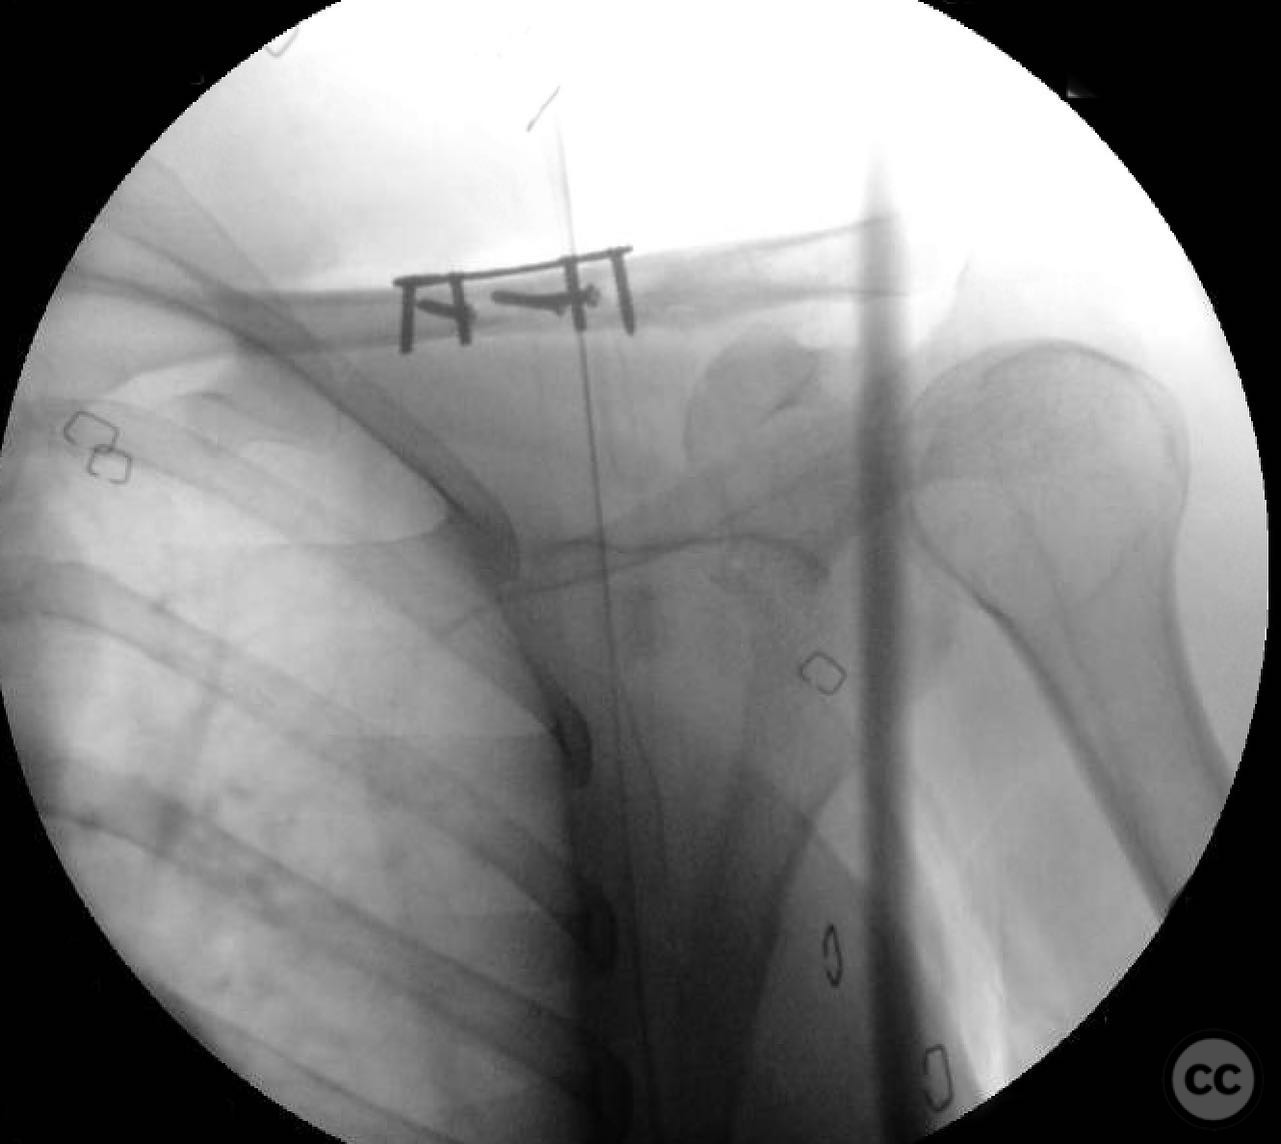

Clinical and radiological findings:  A 35-year-old male presented with an open diaphyseal clavicle fracture following a high-energy motorcycle accident. The fracture was classified as a simple diaphyseal pattern with two butterfly fragments, according to the AO/OTA classification system, specifically 15-B2. The patient exhibited significant soft tissue injury but no neurovascular compromise. Initial radiographs confirmed the fracture pattern, and the wound was thoroughly irrigated and debrided in the emergency department.

Planning remarks:  The preoperative plan involved direct exposure of the fracture site with anatomic clamp reduction. Interfragmentary compression was planned using lag screws for the butterfly fragments, followed by application of a reconstruction plate on the anterior inferior aspect of the clavicle for neutralization.

During the procedure, anatomic reduction of the butterfly fragments was achieved using 2.4mm lag screws for interfragmentary compression. The main segment reduction proved challenging due to instability; hence, a 2.4mm "clamp replacement plate" was temporarily used to maintain reduction. A reconstruction plate was contoured and applied to the anterior inferior clavicle, providing a neutralization construct. Absolute stability was achieved, anticipating primary bone healing.